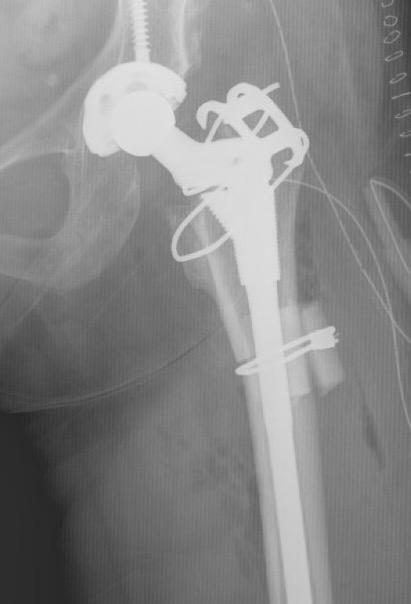

Femoral shortening / Subtrochanteric osteotomy

Technique

Vumedi subtrochanteric osteotomy for Crowe IV

Options

- transverse / oblique / chevron / step cuts

Wang et al J Arthroplasty 2017

- 76 Crowe IV THA

- transverse osteotomy with uncemented stem

- 1/76 nonunion

- 1 acetabulum and 1 femoral stem revised at mean 10 years